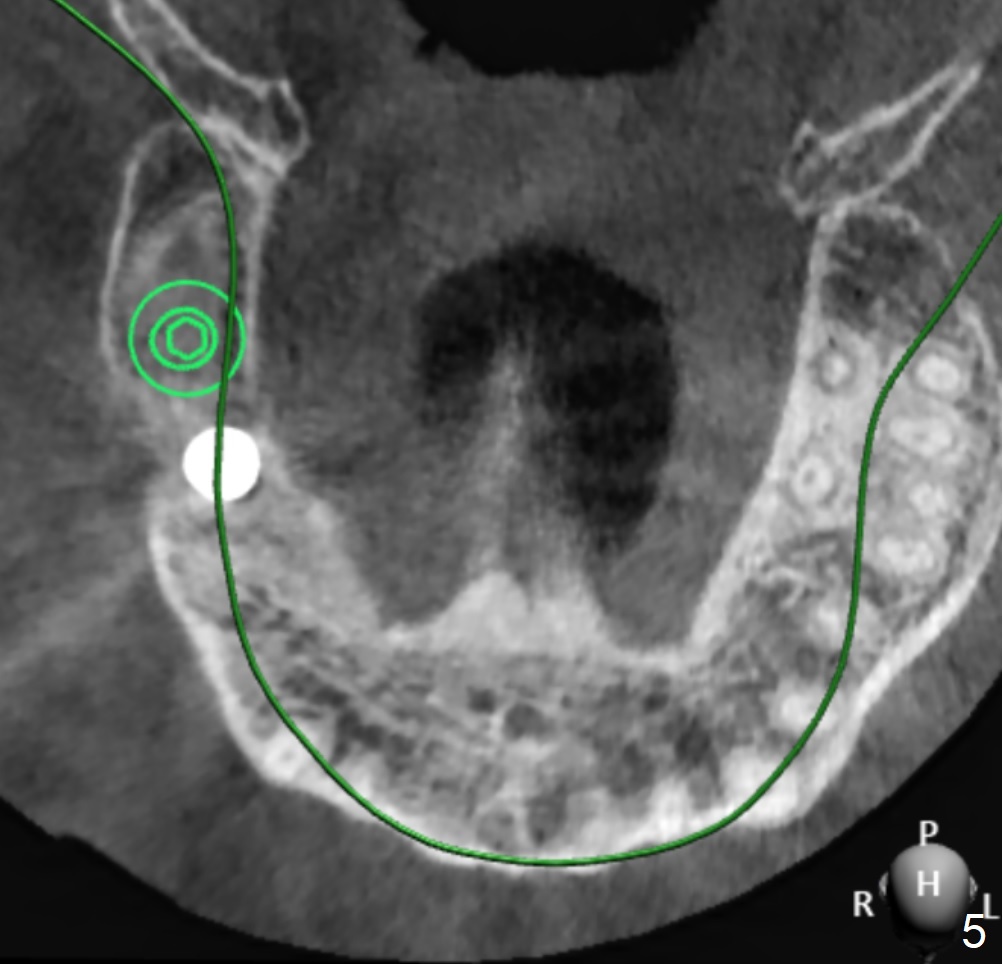

A 52-year-old man wants to have an implant at #2 two years post extraction.

The implant size I tried was 5.0 X 7.3mm and it seems like bone density is quite low.

Undersized drilling suggested (at least 2 size smaller to get more fixation). And on the facial view there's 4mm of remaining bone but on the buccolingual view, there's less than 3mm. It would be much better if you could plan to do a lateral sinus elevation in this case.  Jennifer